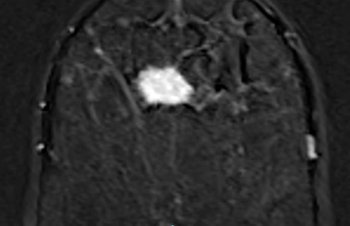

Bei der Magnetresonanztomographie (MRT, MRI, Kernspintomographie) handelt es sich um ein bildgebendes Verfahren, welches mittels einem starkem Magnetfeld und Radiowellen Schichtbilder des Körpers erzeugen kann. Bei dieser Untersuchungsmethode werden keine Röntgenstrahlen verwendet, das verwendete Magnetfeld ist gesundheitlich unbedenklich.

Unsere hochmodernen MRI-Geräte erlauben eine klare und genaue Darstellung von Organen, wie beispielsweise des Gehirns, der Wirbelsäule sowie des gesamten Bewegungsapparates. Wir bieten ein breites Spektrum an MRI-Untersuchungen an allen vier Standorten an.

• MRI des Gehirns und des Rückenmarks